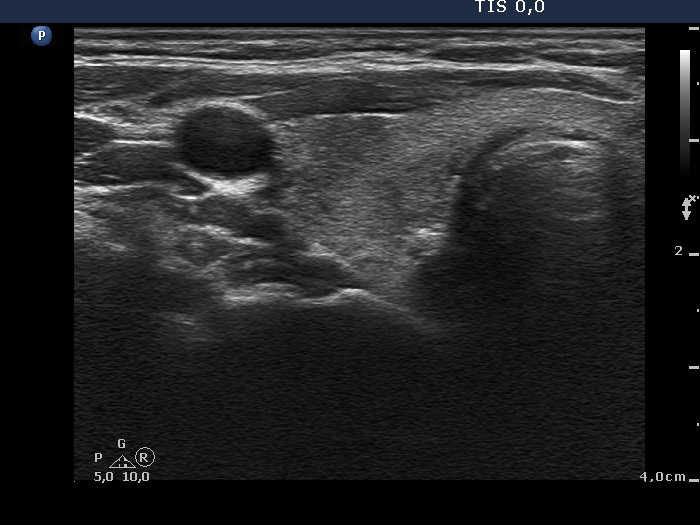

Initial examination (first row of images):

Ultrasonography: The thyroid presented with hypoechoic areas which had blurred borders. The echogenicity index was approximately 65% in the right and 20% in the left lobe. The thyroid was almost completely avascular.